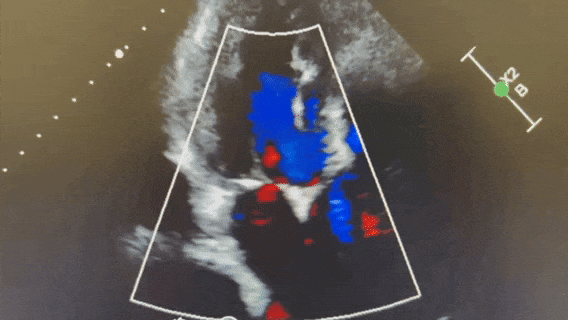

术后超声

术后即时食道超声示:主动脉瓣未见瓣周漏,生物瓣功能良好,未见明显反流。

术后床旁超声描述:主动脉瓣生物瓣膜置换术+二尖瓣成形术+升主动脉成形术后:主动脉瓣位生物瓣位置、形态、回声、活动未见明显异常,瓣周未见明显回声中断,二尖瓣成形术后可见二尖瓣瓣环强回声结构,二尖瓣开放及关闭均未见明显异常。